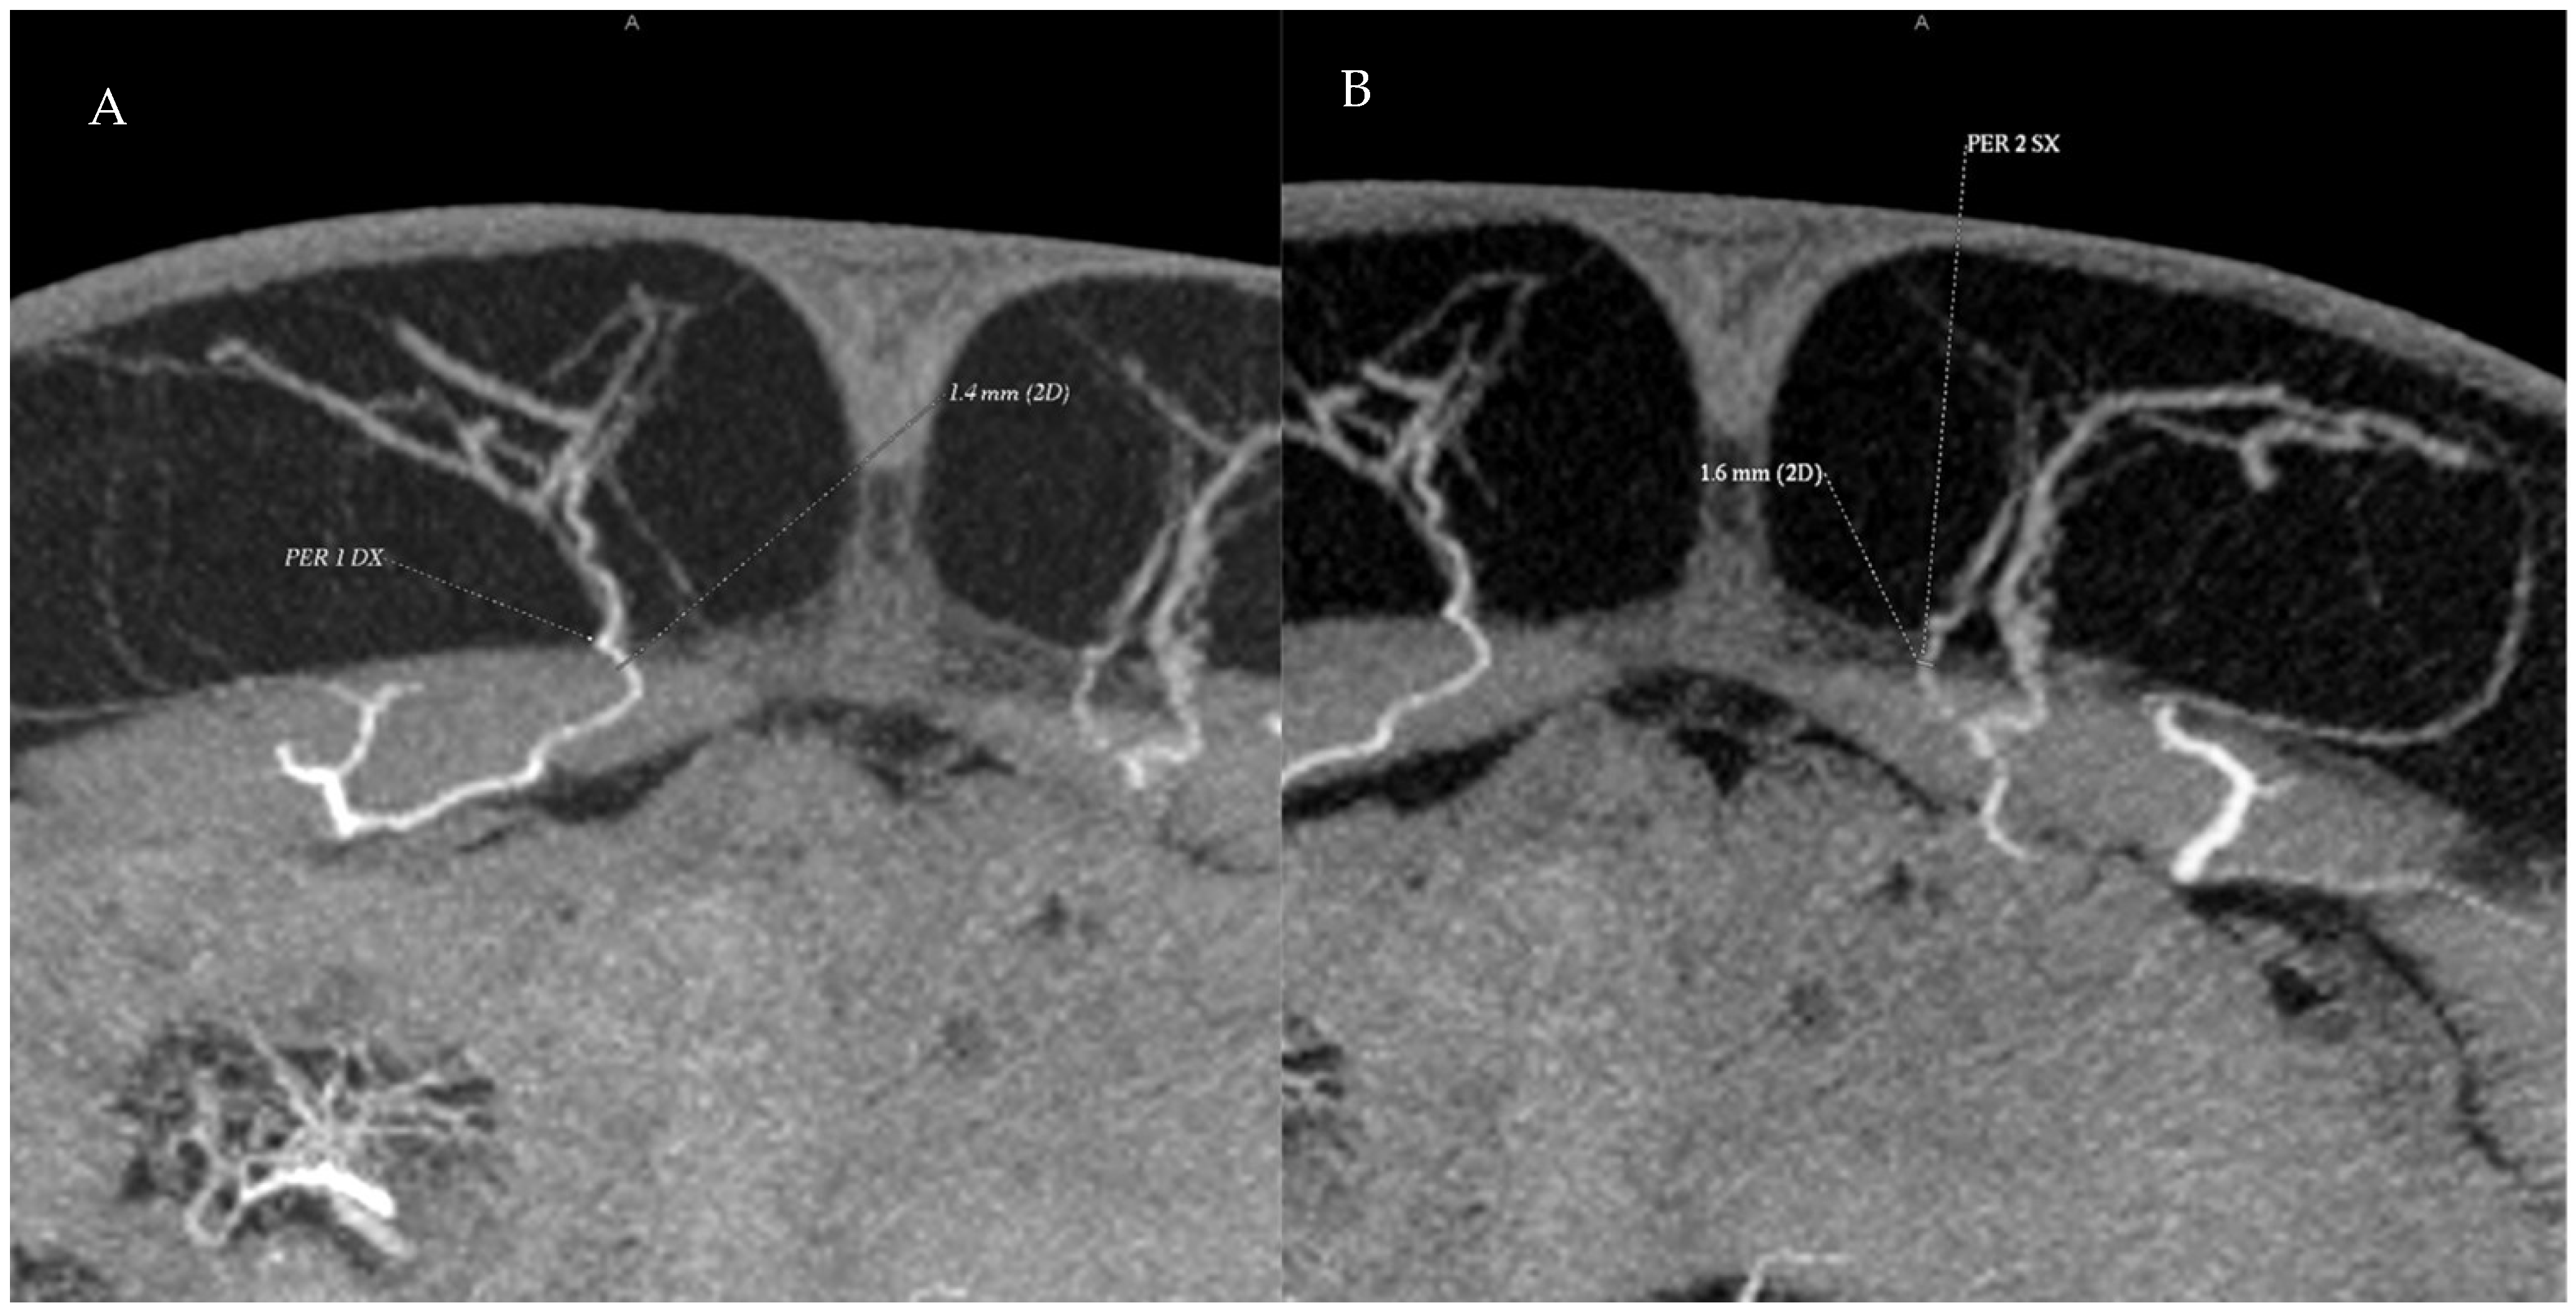

Figure 4. Preoperative CTA images showing the perforating vessels of the deep inferior epigastric artery in the periumbilical region. (A) A single right-side perforator with a diameter of 1.4 mm is identified. (B) Two adjacent left-side perforators are visible; the more medial perforator measures 1.8 mm in diameter.